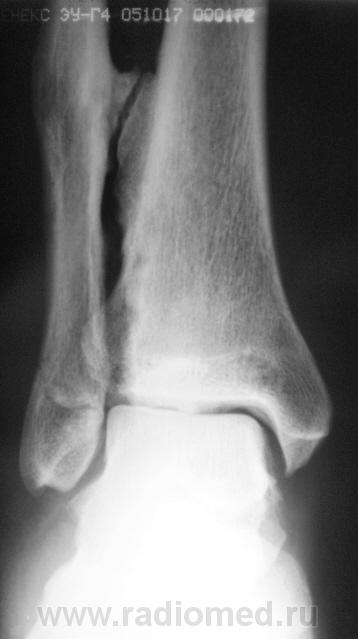

Пациент, в течение последних 2-х лет, жалуется на боли в нижней трети голени. Сегодня, хирургом, пациентка направлена на рентгенографию костей дистальной трети голени и голеностопного сустава. Что посоветуете уважаемые коллеги?

А что здесь советевать? Межберцовый неоартроз, вероятно, травматического генеза. Косой перелом н/л с признаками неполной консолидации. Попробуйте при производстве боковых снимков г/ст с-ва ( при травме) приподнимать пятку на 2-3 см.

Неоартроз между экзостозами? А что это за вздутие м/б кости на уровне неоартроза и пятнистость наружного кортикала? Следствие хронической воспалительной реакции?

Доброй ночи! Разволокнение коркового слоя, нечеткий очаг деструкции. Правда, нет секвестра. Если на увеличении не пригрезилось, то и линейный периостит. Вообще-то ответ был интуитивный, без логических обоснований. Ошиблась?

Какая-то непонятная структура костной ткани в области задней лодыжки.

Некоторая порозность, вероятно, нарушение трофики

В области внутренней лодыжки тоже пороз.